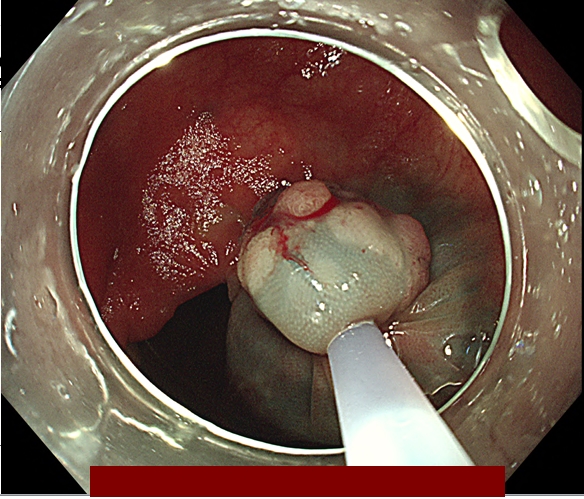

따라서 용종 절제를 하는 주된 이유 2가지는

① 모든 암성 조직을 완전하게 제거하기 위함이고

② 조직학적으로 평가될 수 있는 조직 샘플을 제공하기 위함입니다.

다음은 대장내시경 중 발견된 용종을 일괄 절제한 과정입니다.